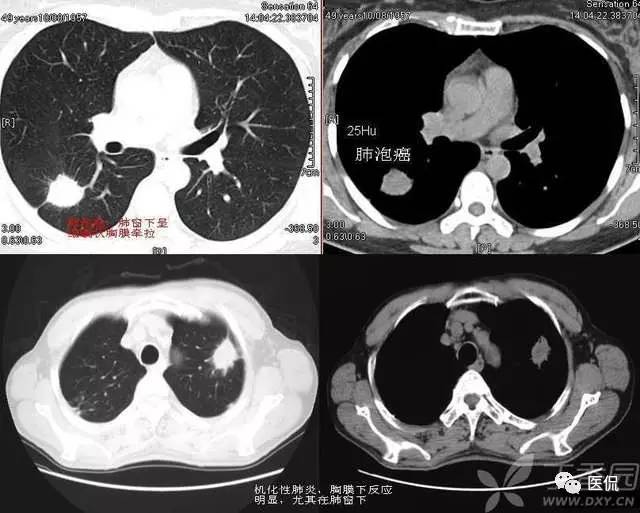

1)肺腺癌:

2)含铁血黄素沉着症:

3)特发性肺间质纤维化: